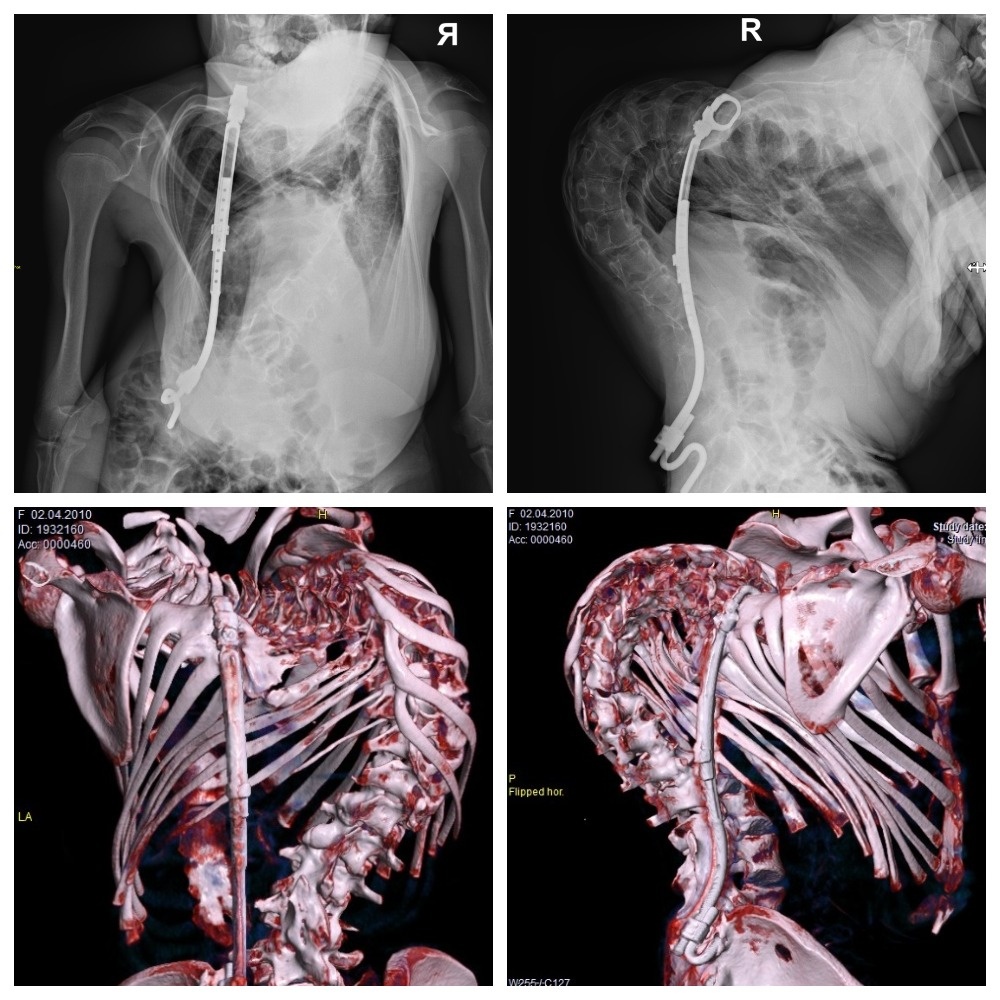

До финальной операции

«В 2016 году выраженность сколиотической деформации позвоночника Надежды достигла более 120 градусов (грудной кифоз – до 130 градусов) на тот момент ребёнку было всего 6 лет. Поскольку ребёнок ещё маленький, было принято решение о многоэтапном оперативном лечении методом растущих конструкций.

Растущая конструкция представляет собой стальной стержень с титановым покрытием, который фиксируется за ребро, позвоночник вверху и позвоночник или таз внизу. Хирурги поэтапно удлиняют устройство — по мере роста пациента примерно раз в год, поскольку изменение длины и формы эндокорректора должно соответствовать форме и длине тела ребёнка.

«На финальном этапе мы поставили несколько нестандартную систему — использовали комбинацию методов фиксации позвоночника. Металлическая конструкция дополнена третьим стержнем, что связано с крайней степенью выраженности деформации и низкой прочностью костной ткани.

Чем больше элементов установлено в данном случае (у паралитического сколиоза есть свои особенности) — тем надежнее фиксация позвоночника в послеоперационном периоде. При этом подход к оперативному лечению один — создаётся жёсткая фиксация с максимальным количеством точек опоры и с блокированием деформированной части позвоночника»,

— комментирует Василий Суздалов.

Благодаря хирургическому лечению достигнута оптимальная коррекция деформации

По мере этапных коррекций рост Нади увеличивался примерно на 2 см, а после финальной операции она выросла с 134 до 146 см. Получена оптимальная коррекция деформации (сколиоз – до 66 градусов, грудной кифоз – 80 градусов), а также коррекция баланса туловища.